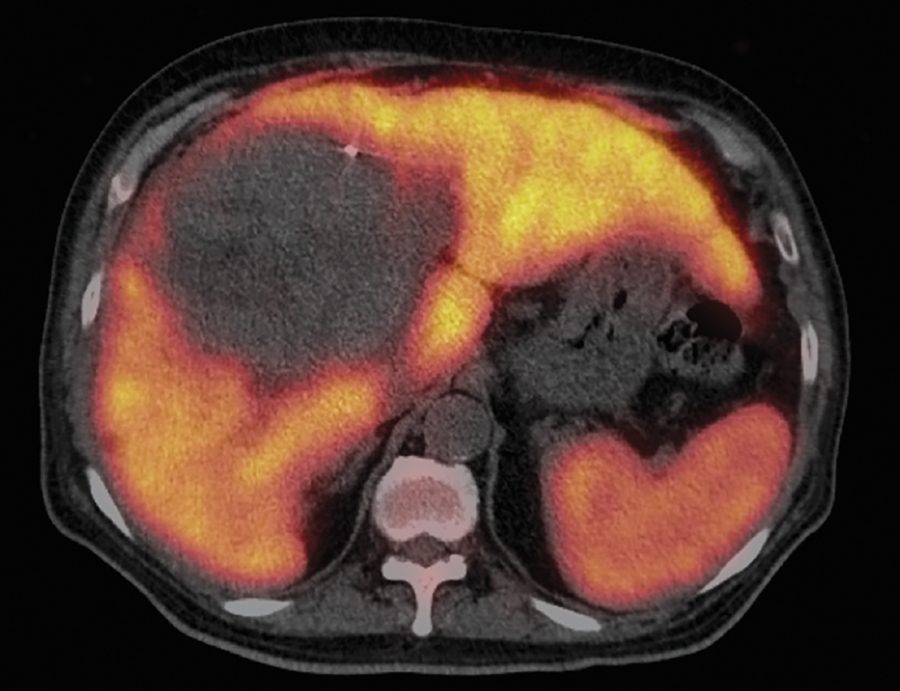

Radioterapia para el cáncer de hígado